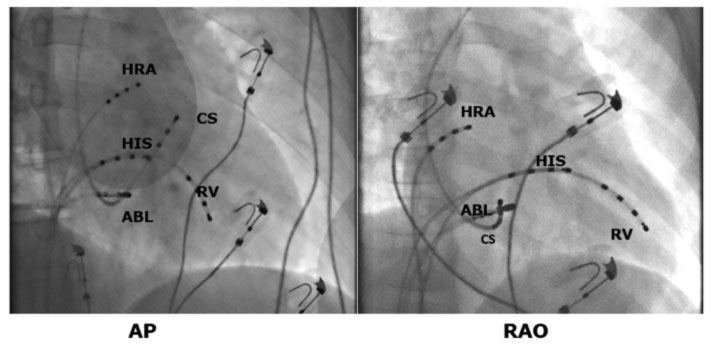

Per l’ablazione della via lenta sono possibili due diversi tipi di di approccio: tramite mappaggio elettrofisiologico o anatomico. In entrambi i casi vengono prima identificati i limiti anatomici del triangolo di Koch posizionando un catetere sull’His ed uno nel Seno coronarico. Il catetere ablatore viene poi fatto avanzare attraverso la vena femorale fino all’anulus tricuspidalico in prossimità dell’ostio del seno coronarico (CS).